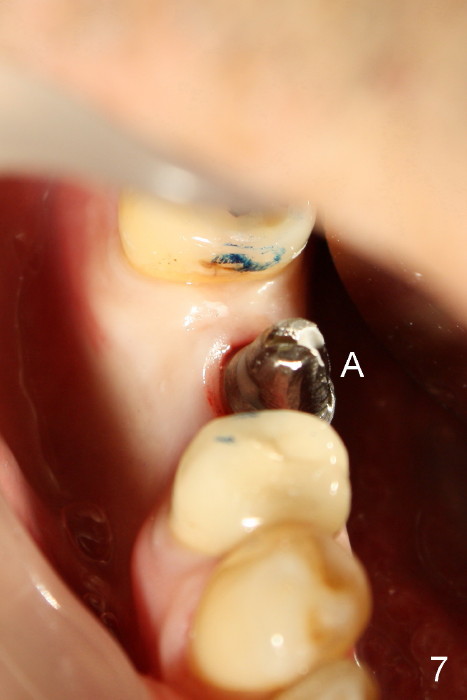

五十多岁的吴先生右下六有根分叉感染(图一),有一次到外地出差疼痛难忍拔除了,一两年后才同意植牙,图二显示已经愈合近远中(M, D)牙槽窝,六乘十七毫米植牙(图三I)好像种得很端正,其实并不完全是这样。让我们回到图二,沿着虚线做个冠状切面,显示右上六号牙以及右下六牙槽骨(图四*),与对侧六号牙冠状切面(图五)对比,右下六牙槽骨往舌侧(L)倾斜(B:颊侧),要植入长而宽的植牙,它就往舌侧倾斜(图八)。为了与对侧牙齿咬合,必须用二十度倾斜的基牙(图六A),但是临床上通过基牙而改变的角度还不够(图七),所以最后牙冠(图十C)不在植牙(I)长轴上,也就是一部分牙冠是悬臂的(*),容易造成陶瓷断裂,基牙松动。避免悬臂牙冠最好的方法便是拔牙后即刻植牙(图九),如果骨质已经吸收,植骨(图十一红色)或者骨扩张时尽量让颊侧骨板往颊侧移动,纠正植牙倾斜角度。